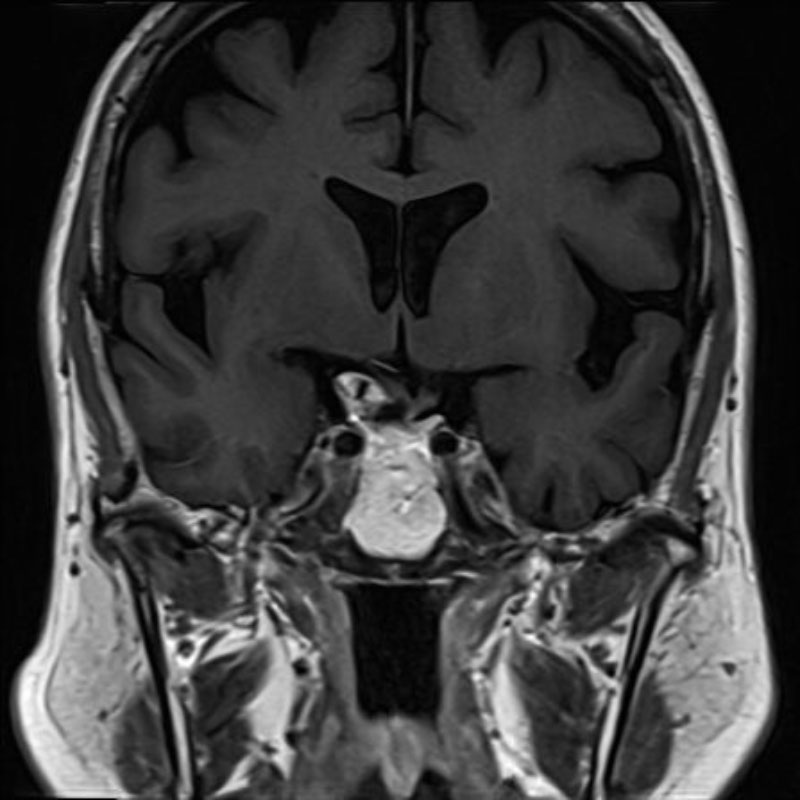

'24年10月

50代

頭蓋咽頭腫

頭蓋内腫瘍摘出術